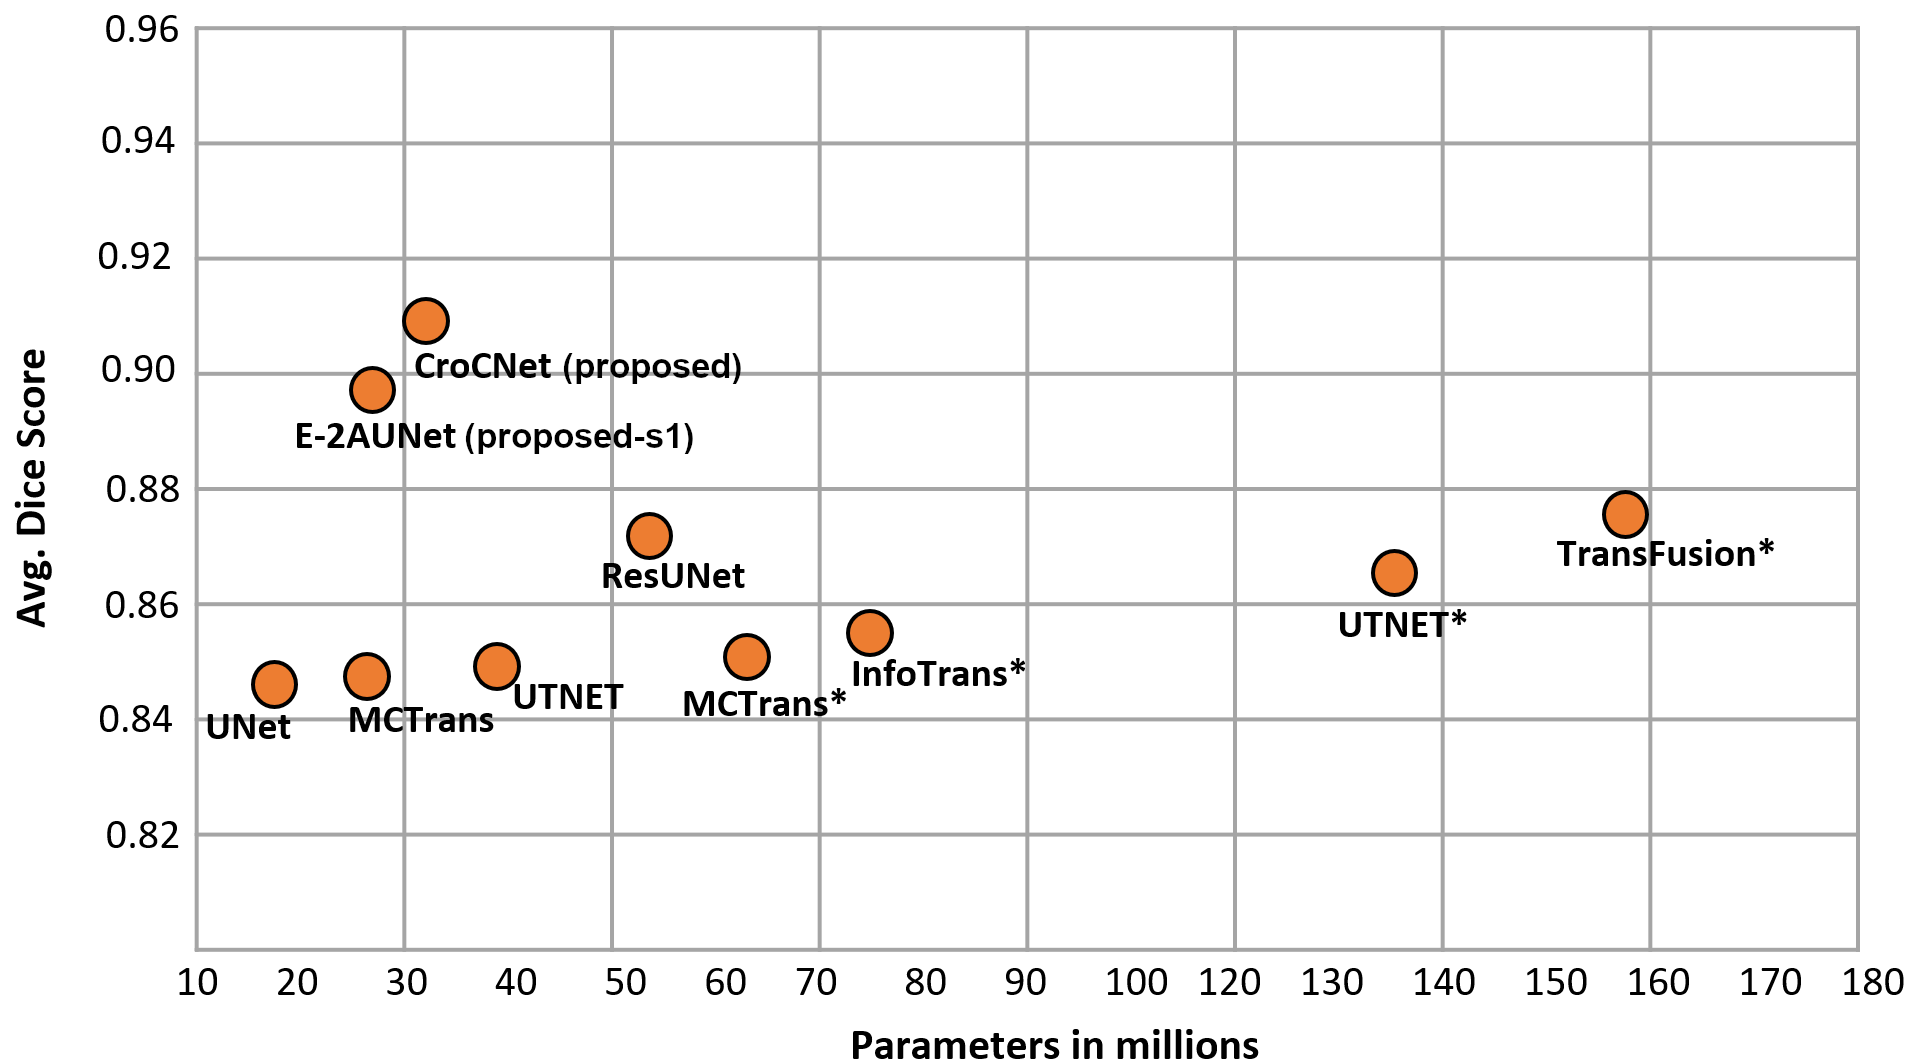

and hybrid utilizing both CNN and MHSA. Fig. 5 depicts the computational complexity of the proposed pipeline compared to existing methods. Results are provided from both stages, i.e. stage 1 (Proposed-s1) and 2 (CroCNet). Notably, the proposed method outperforms existing networks, even at stage 1. The stage 2 network contributes to further refinement, correcting erroneous predictions, as visually depicted in Fig. 3. In Fig. 3, the first column shows some erroneous segmentation examples of stage 1 networks. The middle column demonstrates the improvement achieved by the second stage in refining predictions from the first stage. The rightmost column provides the reference ground truth. Additionally, rows (a) and (b) depict how the cropping mechanism aids in removing outliers. Finally, observation from rows (c) and (d) shows that the cross E-2A among the encoder’s features of LV-Net, RV-Net, and MYO-Net contributes to further enhance the segmentation maps, particularly addressing disconnected edges in the areas of interest.